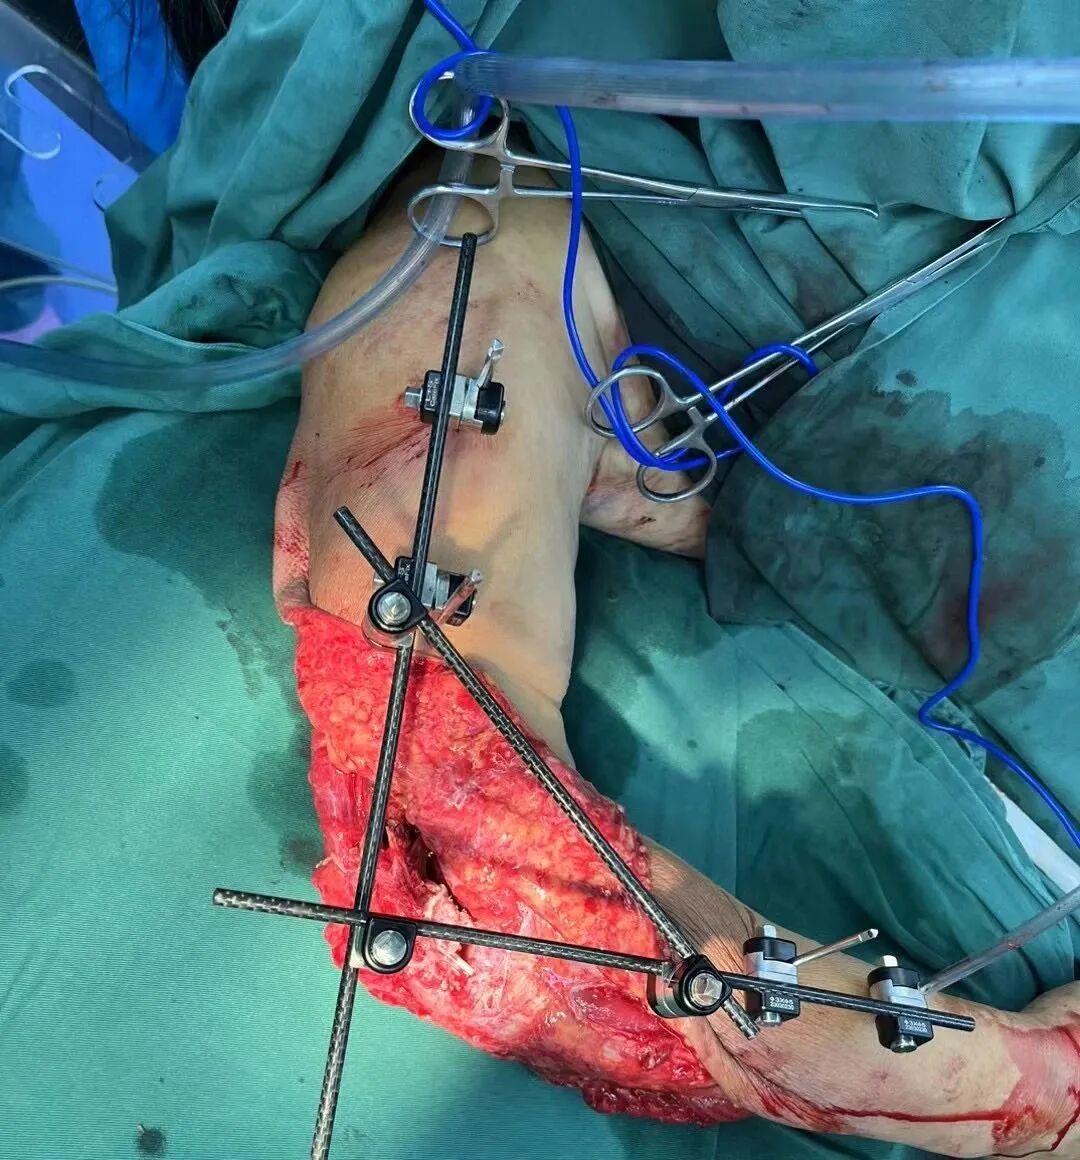

多学科联动 成功救治车祸重伤患者

近日,陕西冶金医院急诊医学科接120通知,灞桥区半引路附近突发一起交通事故。一女子被渣土车拖挂,导致右肘皮肤肌肉挫裂伤、血管严重挫伤。伤者被120送至陕西冶金医院急诊医学科后,已经等候在现场的骨科、重症医学科、手术麻醉科等多学科专家立即会诊,同时迅速开辟“绿色通道”,为患者建立静脉通道并完善相关检查。综合各项检查结果,患者家属签署知情同意书后,在骨科赵学刚主任带队下行:右上肢大面积损伤肌肉、皮肤清创,血管神经肌腱探查修复术,VSD持续负压引流术,骨折复位外固定架固定术。手术顺利完成,目前患者生命体征平稳,已转入骨科继续治疗。

紧急抢救离不开团队协作,多学科联合救治已成为陕西冶金医院救治复杂、疑难、危重患者的常规模式。此次无缝隙接力救治,充分体现了多学科精诚协作为患者保驾护航的理念,是对医院处理急、危、重、复合性创伤等高危复杂患者综合救治能力的再一次检验。